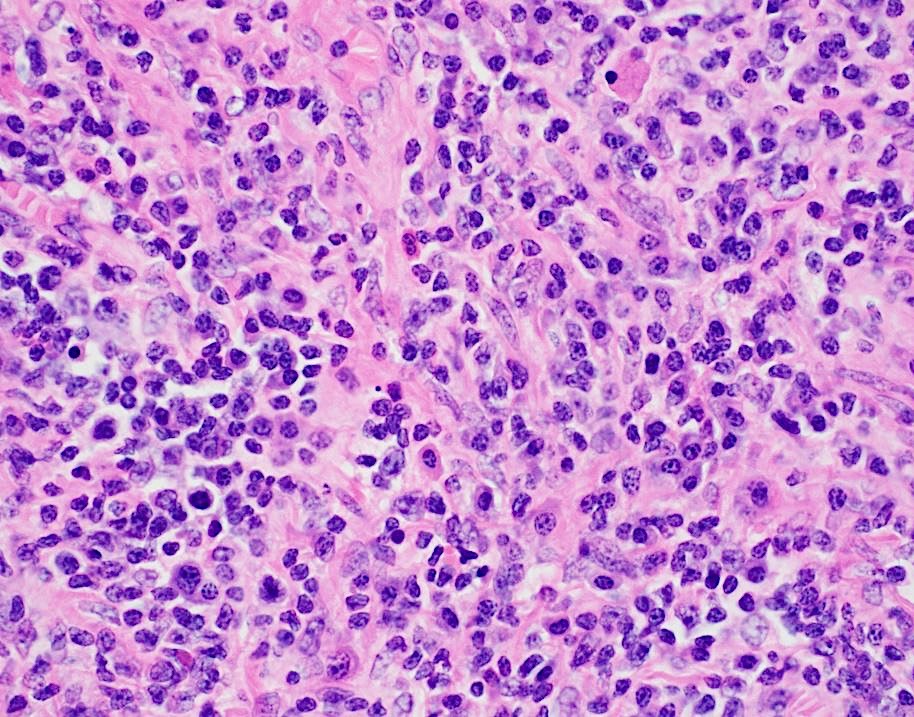

Tissue sections show a diffuse atypical lymphoid infiltrate that completely effaces the normal nodal architecture. The infiltrate is composed of numerous small lymphocytes with round to mildly irregular nuclei, clumped chromatin, inconspicuous nucleoli and scant cytoplasm. There are also expanded pale areas that contain intermediate sized cells with more open chromatin and distinct single to multiple nucleoli. These cells are most consistent with prolymphocytes/paraimmunoblasts and form the proliferation centers characteristic of CLL/SLL. Occasional centroblastic-type B-cells are noted within these proliferation centers. In addition, there are scattered single to multinucleated cells that have irregular nuclear membranes with pale, vesicular chromatin and prominent inclusion-like, eosinophilic nucleoli. These cells morphologically resemble Hodgkin cells, Reed-Sternberg cells, mummified forms and other variants. These large cells are more evident in areas with a histiocyte rich background and around foci of necrosis. Occasionally, apoptotic bodies and mitotic figures are seen.

Immunohistochemical studies show that the vast majority of the small-intermediate lymphocytes express B-cell markers CD20 (dim) and PAX5 and co-express CD5 and CD23 (subset). This is consistent with a background of CLL/SLL. The large atypical cells are positive for CD30, PAX5 and CD20 (variable). CD3 highlights numerous scattered background small T-cells, which are increased in the areas with the large cells. In situ hybridization for Epstein Barr viral RNA (EBER ISH) is mainly staining the large atypical cells. By Ki-67, the proliferation fraction is overall increased (40%) with increased uptake by the large atypical cells.

The morphologic and immunophenotypic findings are consistent with involvement by the patient’s known small lymphocytic lymphoma/chronic lymphocytic leukemia (SLL/CLL) with aggressive morphological features. The aggressive features include expanded proliferation centers and an elevated Ki-67 proliferative index (40%). Additionally there are histiocyte/T-cell rich areas composed of multiple EBV positive large atypical cells with morphologic and immunophenotypic features compatible with Hodgkin/ Reed-Sternberg cells. These areas are most in keeping with evolving classic Hodgkin lymphoma. Sheets of large cells indicative of large cell transformation are not seen, although increased scattered large centroblastic-type B cells are present.

Aggressive features of CLL/SLL include proliferation centers that are broader than a 20x field or becoming confluent. An increased Ki-67 proliferation >40% or >2.4 mitoses in the proliferation centers can also portend a more aggressive course. These cases tend to have worse outcomes than typical CLL/SLL and better outcomes than cases that have undergone Richter transformation to diffuse large B-cell lymphoma (DLBCL). Transformation to DLBCL occurs in 2-8% of patients with CLL/SLL. Less than 1% of patients with CLL/SLL develop classic Hodgkin lymphoma (CHL). In order to diagnose CHL in the setting of CLL/SLL, classic Reed-Sternberg cells need to be found in a background appropriate for CHL, which includes a mixed inflammatory background. The majority of these CHL cases will be positive for EBV.1